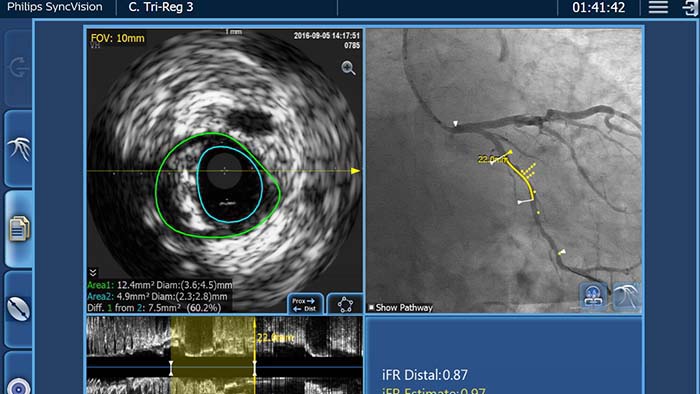

with the angiogram using iFR Co-registration, IVUS Co-registration and Tri-registration features6

Built on a smart, applications-based platform that can scale to meet the evolving needs of your lab when new applications or modalities become available, without the need to purchase new hardware. Only Philips Interventional Applications Platform - IntraSight,6 offers best-in-class imaging and physiology tools with iFR, iFR Co-registration, FFR, IVUS, IVUS Co-registration, and Angio+. With its modular architecture, IntraSight stays on top of latest advances and important security updates.

the gold standard among resting indices because it’s backed by patient outcomes, that reduces costs, procedural time and patient discomfort1-3 while providing advance guidance with co-registration. With iFR Co-registration there is no need for hyperemic drugs and no need for guesswork.

The IntraSight Interventional Applications Workspace is where imaging, physiology, co-registration* and software all come together to clearly identify coronary and peripheral artery disease, and allow for more optimized treatment plans. IntraSight is built on a new foundational platform designed to meet the evolving needs of your lab today and tomorrow.